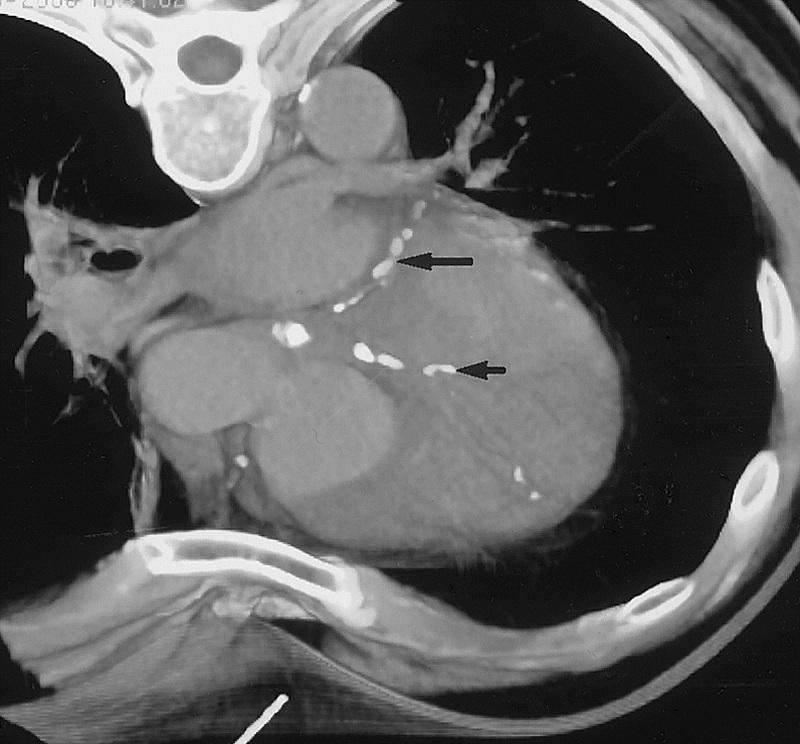

无造影剂ct显示冠状动脉钙化

9病例展示 写美篇病例一: 诊断意见: 1,右冠状动脉近段非钙化型斑块伴